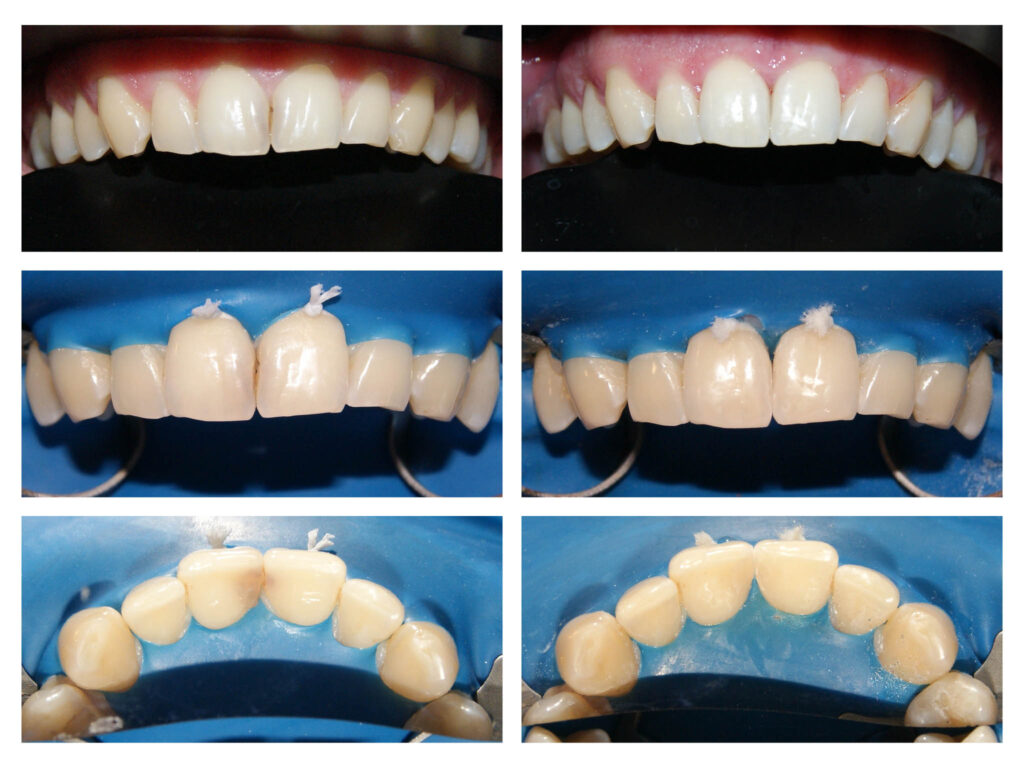

Lucrare protetică din Zirconiu stratificat- integrare estetică- praguri minim invazive pe dinți tineri, vitali – gingii sănătoase